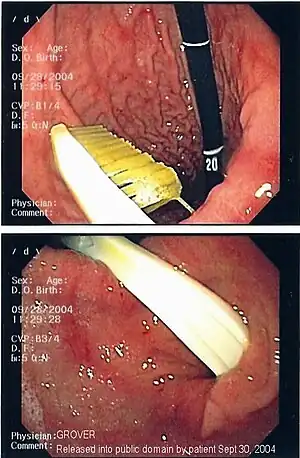

| Endoscopy image of foreign body in the stomach (toothbrush) | |

One of the most common locations for a foreign body is the alimentary tract.

It is possible for foreign bodies to enter the tract from the mouth or rectum.